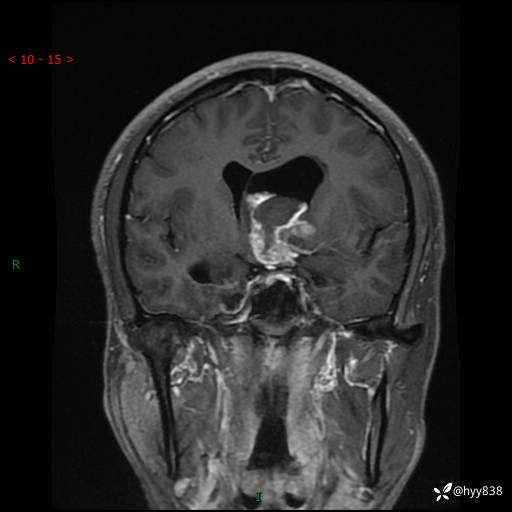

颅脑MRI平扫+增强